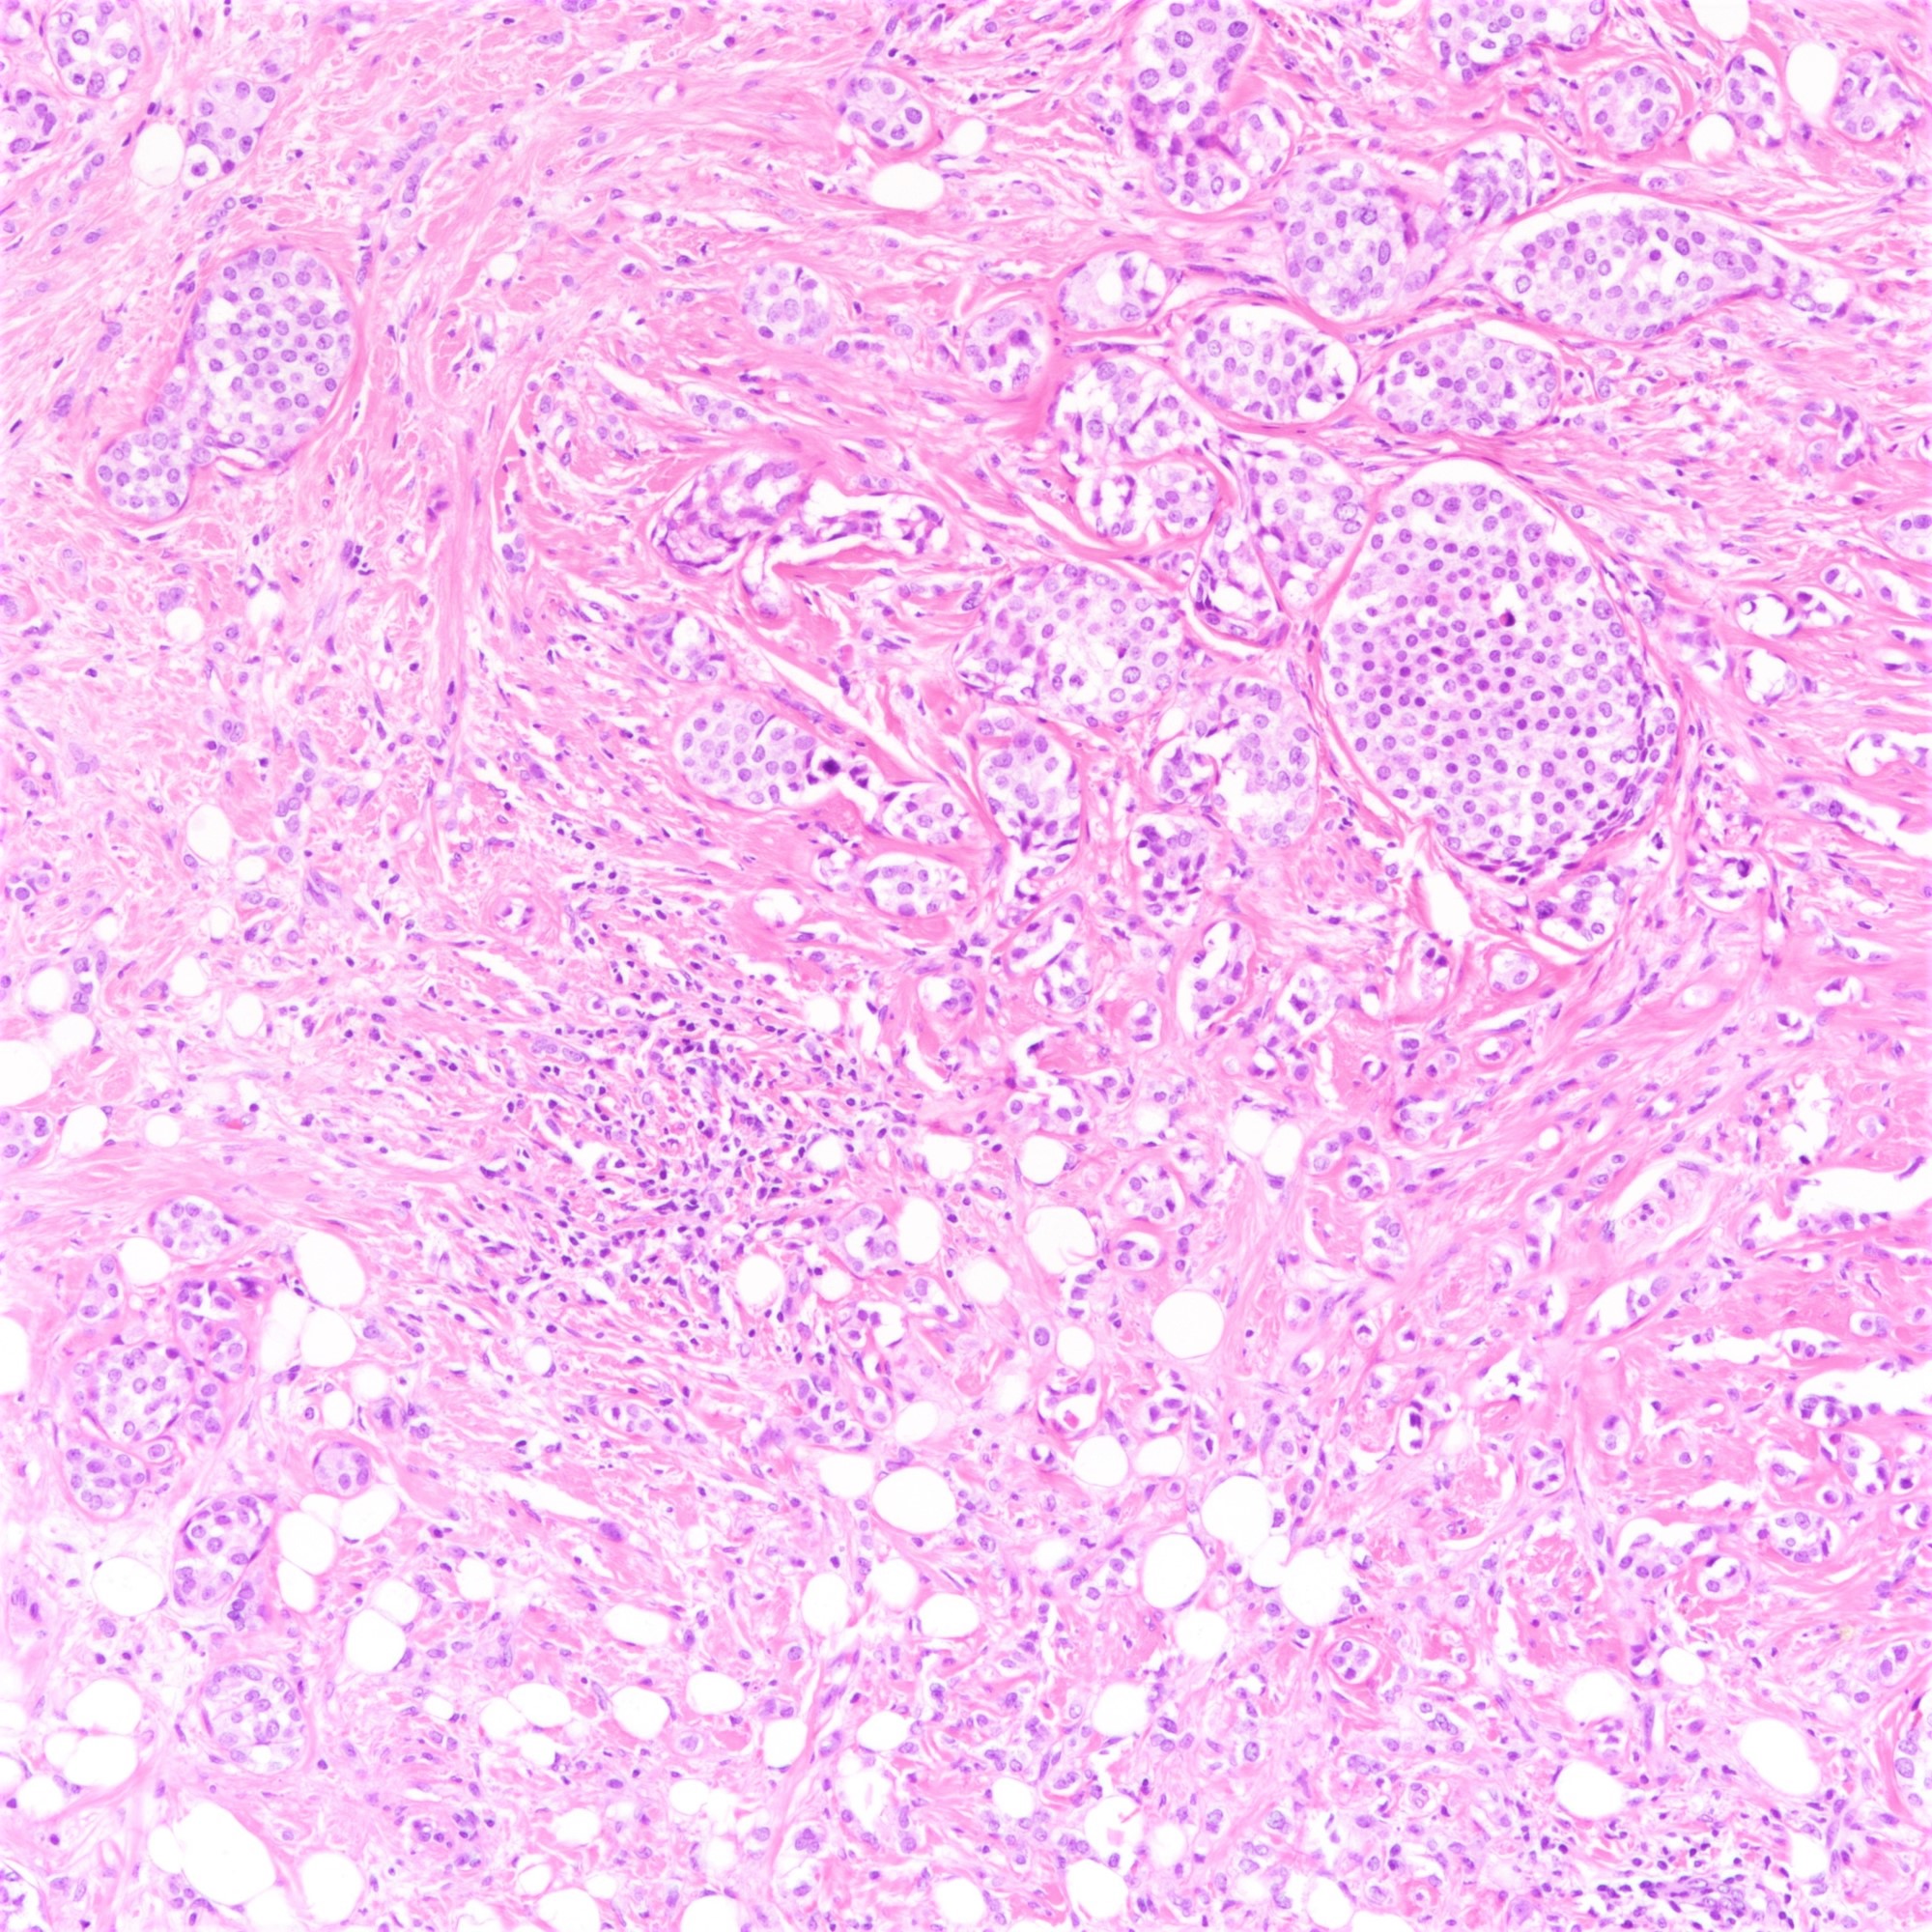

Microscopic (histologic) description

- Tumor cells arranged in single files, cords and single cells (Breast Cancer Res 2015;17:12)

- Can be arranged concentrically around normal ducts, giving a targetoid appearance

- Tumor cells discohesive, small, monomorphic and lacking marked atypia

- Round or notched ovoid nuclei, usually grade 1 or 2 nuclear score

- Scant cytoplasm, occasional with intracytoplasmic lumen

- Mitosis infrequent

- Desmoplastic reaction and necrosis uncommon

- Other (nonclassic) patterns of lobular carcinoma

- Alveolar:

- Clusters and aggregates of ≥ 20 cells

Microscopic (histologic) images